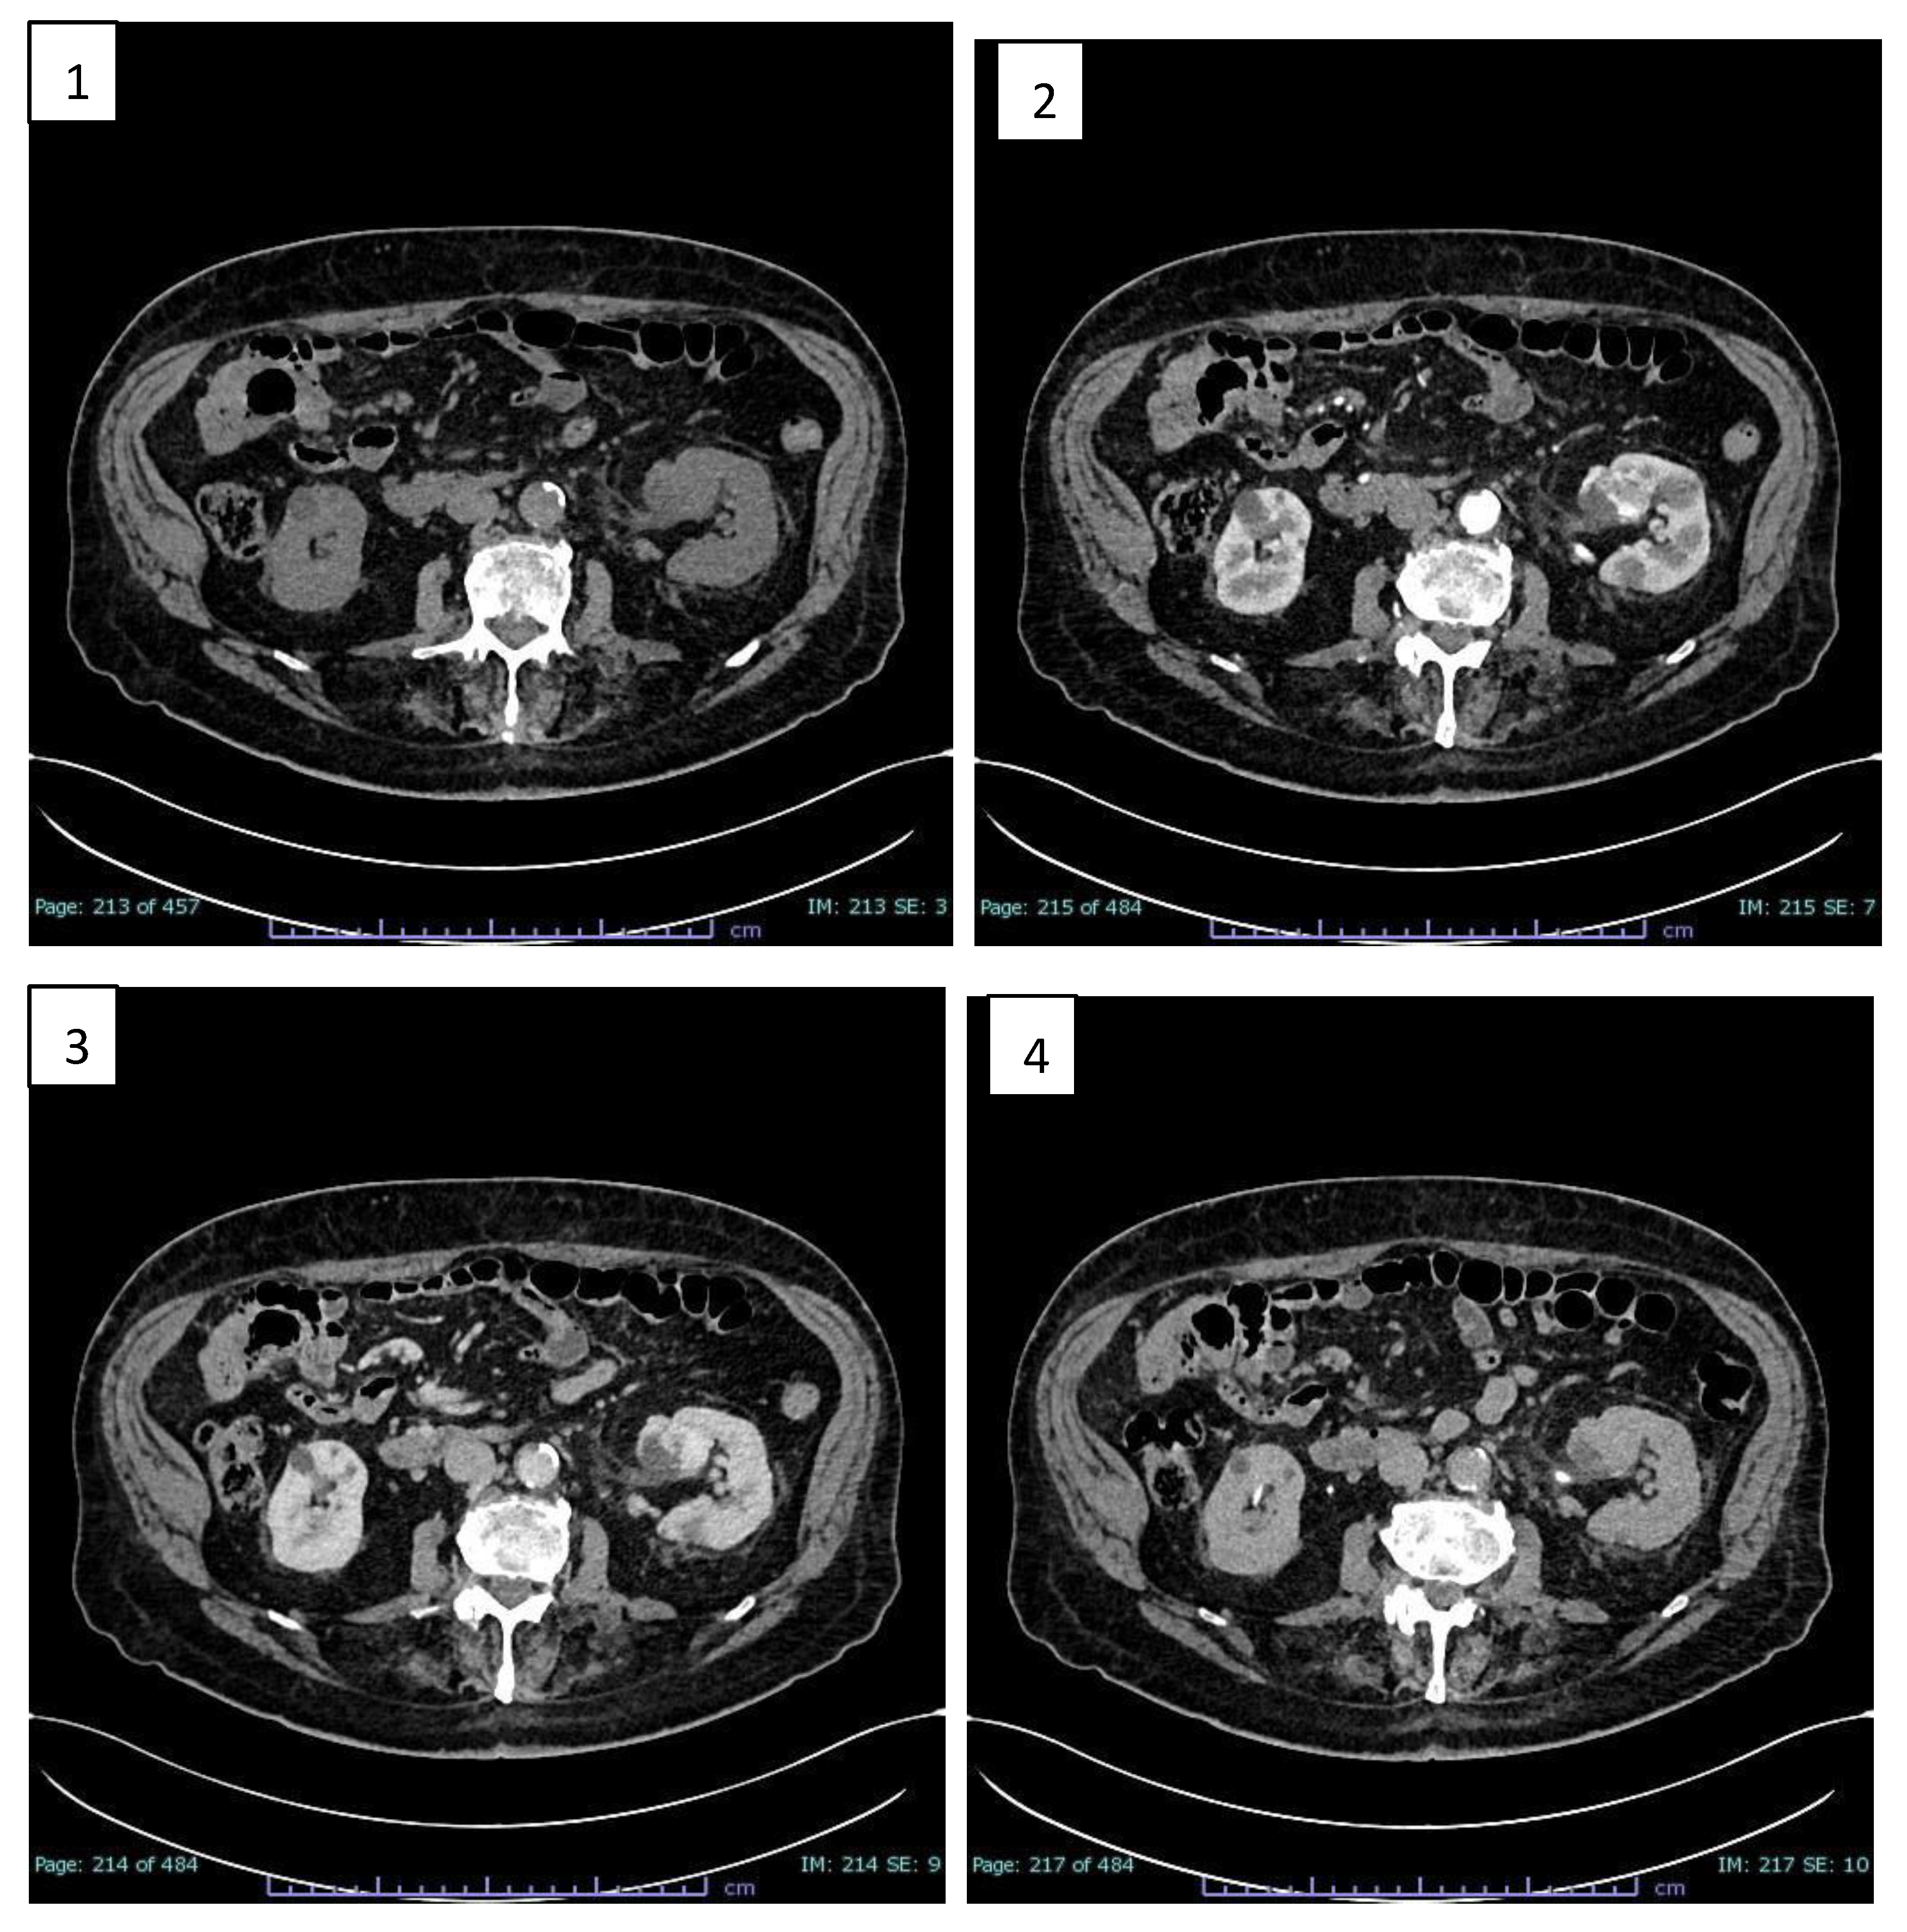

To better characterize the lesion, the patient underwent MRI examination of the upper and lower abdomen without and with intravenous CM (Figure 2).

MRI images showed T1-dependent signal hypointensity (Figure 2.1), inhomogeneous T2-dependent signal hyperintensity (Figure 2.3), and appears to have poor diffusion-weighted signal restriction (Figure 2.4, Figure 2.5). Overall, it is characterised by inhomogeneous contrast impregnation and has a greater axis of 32 x 23 x 26 mm (LL x AP x CC).

This technique confirms that the heteroformation did not generate compressive effects on the renal pelvis or vascular invasion. No significant mesenteric, para-aortic or retroperitoneal lymphadenopathy was evident.

MRI images also show characteristics of inhomogeneous signal intensity, reflecting its vascular nature, revealing signal hypointensity in T1 sequences, inhomogeneous signal hyperintensity in T2 and poor signal restriction in DWI, indicative of poor cellularity.

Figure 2. RM scans before and after enhancing with CM. 1) Axial T1 TFE MRI sequence: heteroformation of the left renal sinus showing T1-dependent signal hypointensity. 2) Axial SPAIR T2 MRI sequence: inhomogeneous T2-dependent signal hyperintensity. 3) Axial DWI sB750 MRI sequence: poor diffusion-weighted signal restriction. 4) Axial ADC MRI sequence.